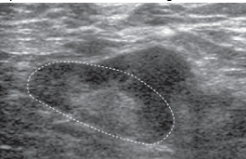

Metastatic lymph nodes

Metastases implant in subcapsular or cortical sinusoids → cortical thickening

- Location of implant determines pattern of thickening

Asymmetric cortical thickening

Very hypoechoic

Round

Microcalcifications

Central necrosis (severe)

Differential = benign reactive node (symmetric cortical thickening)